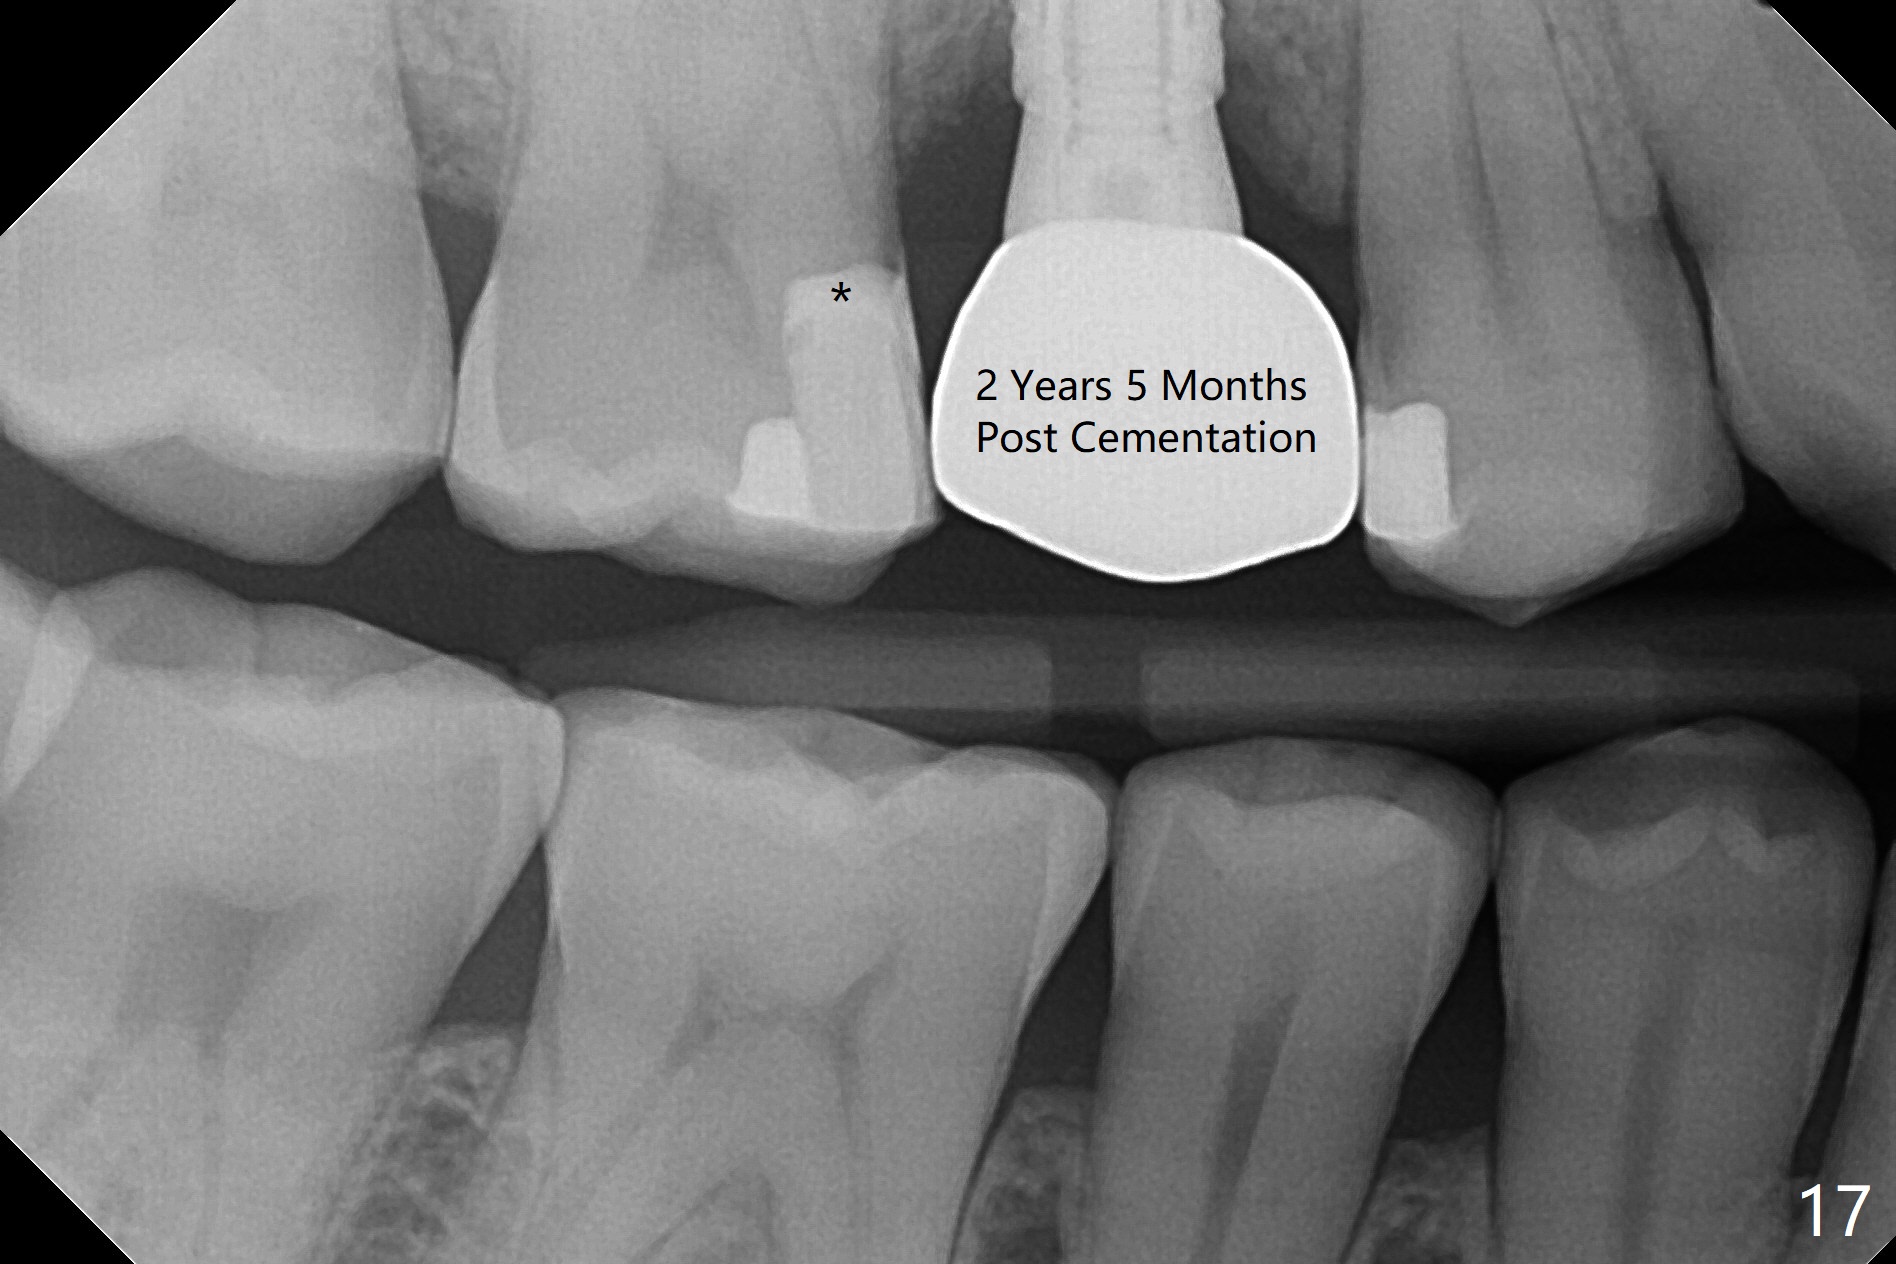

In fact there is a small buccal fistula, which is communicated with the underlying implant threads. Although preop CT shows that the buccal crest is lower than the palatal (3.8x13 mm, Fig.10 P) one, intraop finding of missing buccal plate should dictate a shorter implant (Fig.11) or onlay graft to avoid periimplantitis. Regeneration of the bone plate is limited. Later the fistula disappears with formation of a concavity (Fig.13). There is no symptom. Is bone graft necessary with a remote incision? 3-D images of CT taken 1 year 5 months post cementation show possible mesiobuccal and distopalatal bony defects (Fig.13-16). It is possible that bone graft was placed enough palatal (Fig.16). DO composite at #3 is redo satisfactorily (Fig.17 *).